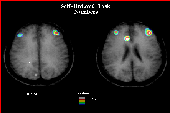

Regional cerebral blood flow was measured with PET during the performance of verbal memory working tasks. In the first experiment, subjects were asked to generate a sequence of 10 unordered numbers using numbers 1 to 10 without repeating a number. For example, "2,6,4,5,3,1,7,9,8,10" would be such a sequence. This is known as a self-ordered task memory. In the second experiment, the subject was asked to monitor a sequence of 9 numbers from 1 to 10 which were generated by the experimenter. One number was intentionally omitted and the subject was asked to report which number was omitted. This is known as externally ordered task memory. These experiments require the subject to maintain all the numbers that have already been used in working memory.

Examination of the difference in activation between these conditions revealed strong bilateral activation within the mid-dorsolateral frontal cortex during both experimental tasks. There was, however, no evidence of additional activation within the mid-dorsolateral frontal cortex when monitoring self-generated responses as compared with the monitoring of externally generated responses (See Figures 9 and 10). These results provide evidence regarding the role of the mid-dorsolateral frontal cortex in mnemonic processing that are in agreement with recent findings from work with non-human primates.

Figure 9: Activation of frontal cortex resulting from the patient undergoind a self-ordered task.

Figure 10: Activation of frontal cortex resulting from the patient undergoind a self-ordered task.